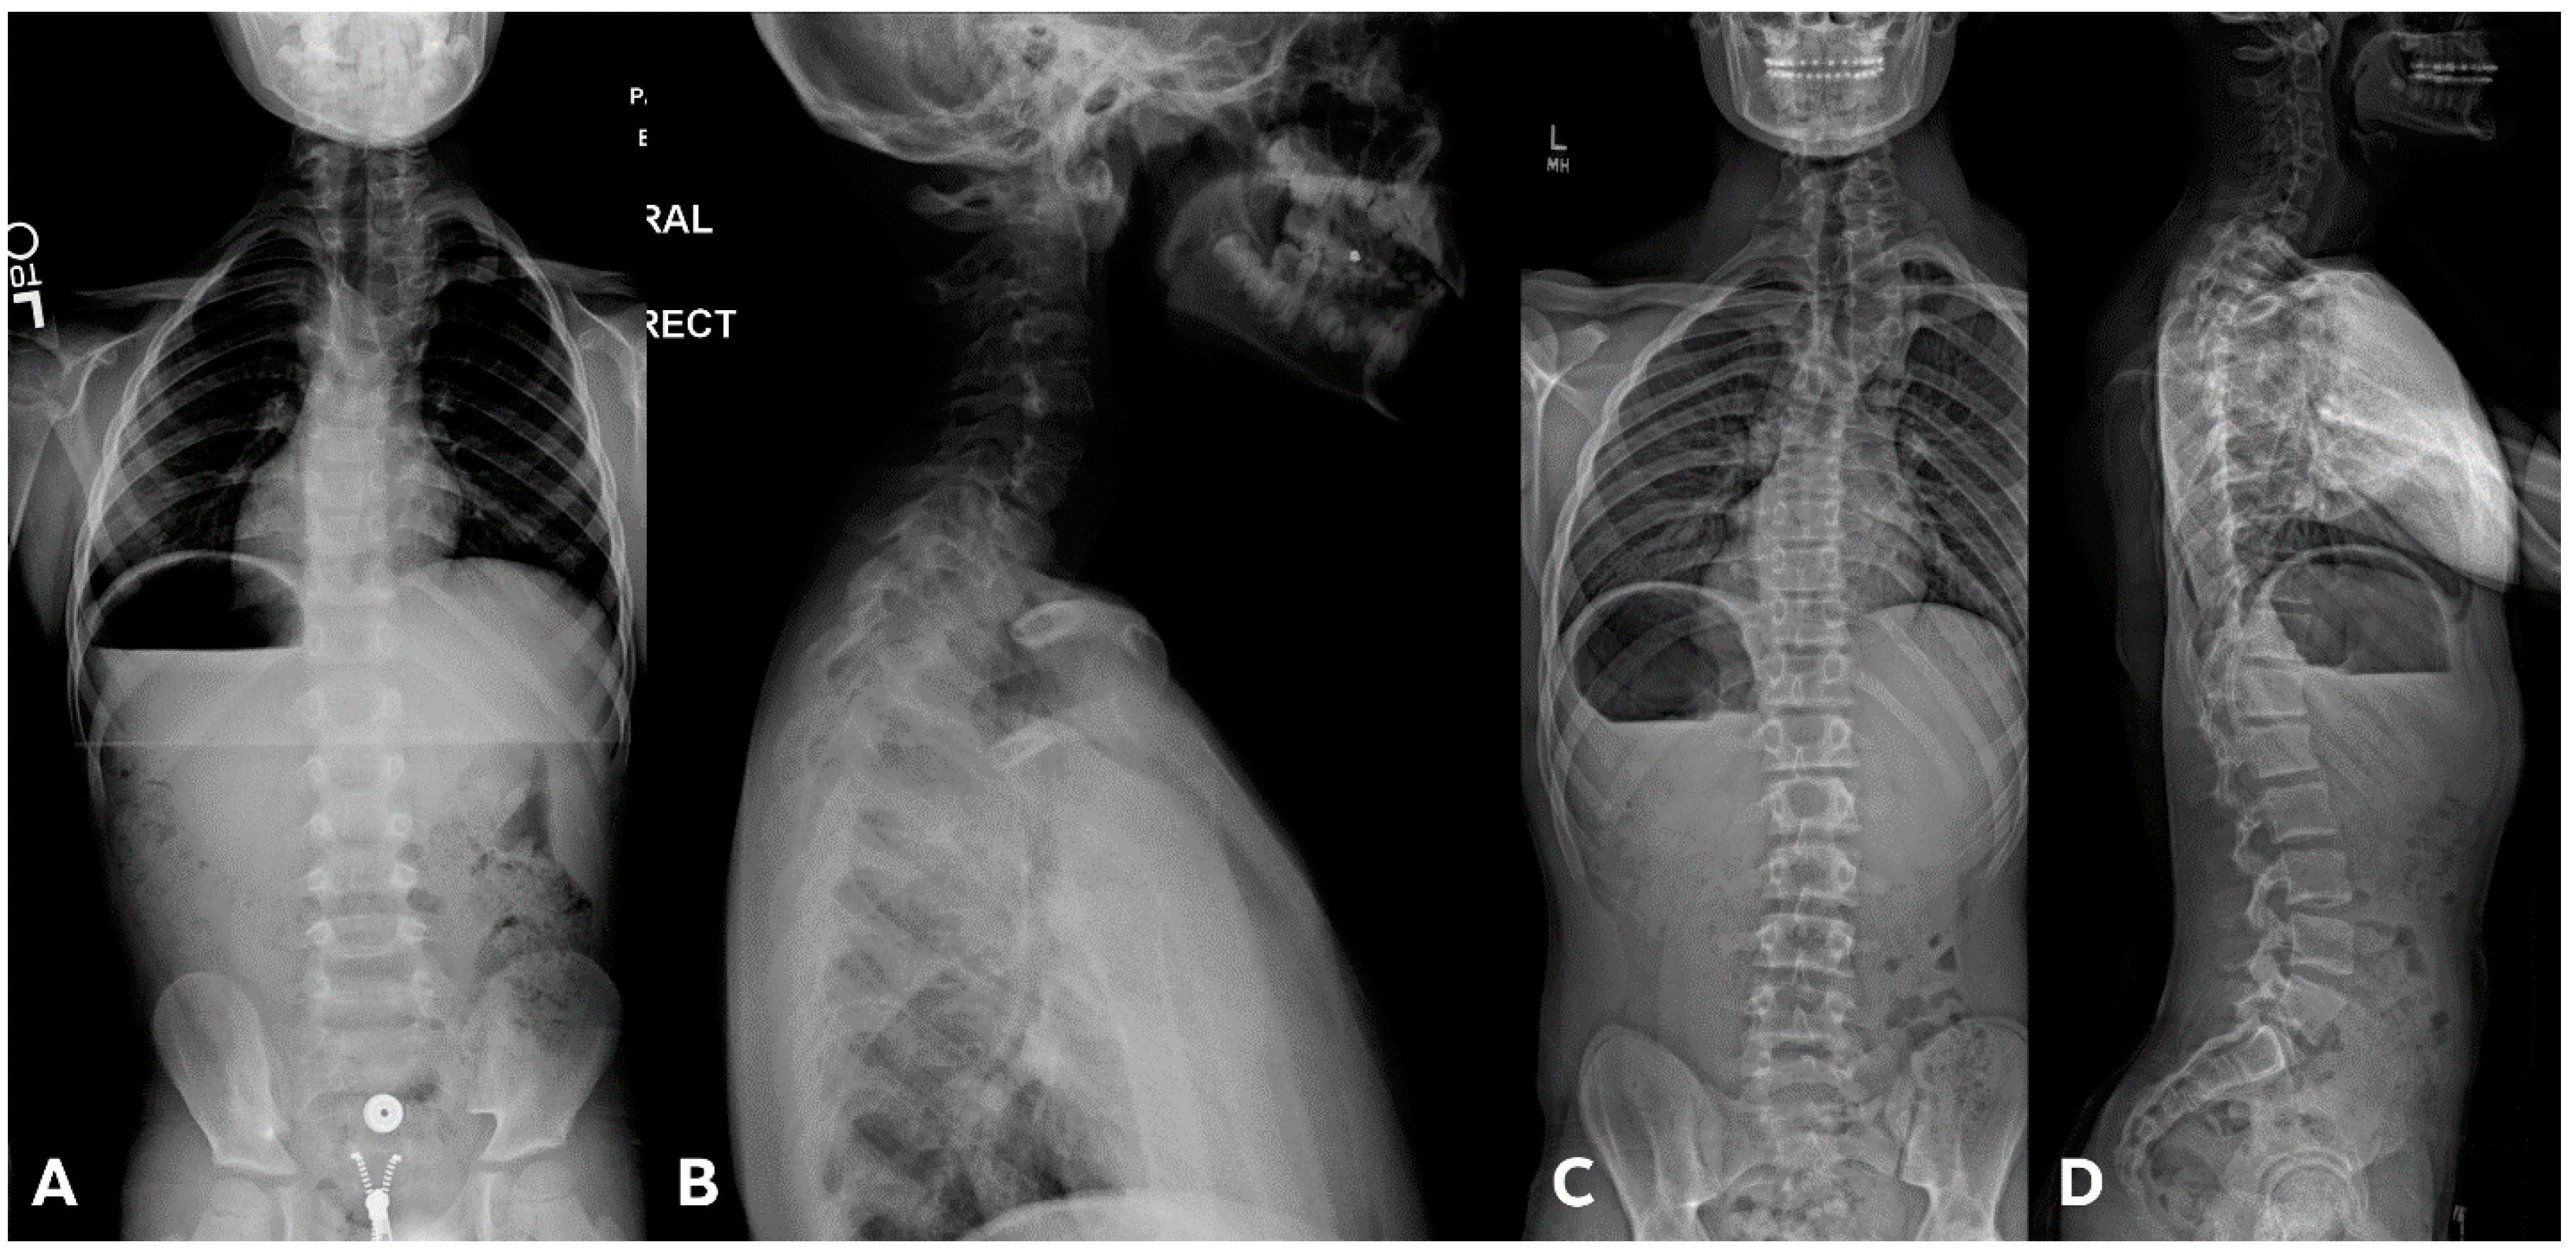

Figure 5.

(A,B) Initial PA and lateral radiograph of a 7-year-old child with a 19° cervicothoracic scoliosis and T1 slope of 31°. (C,D) Follow-up PA and lateral radiographs showing progression of the curve to 38° over 8 years.